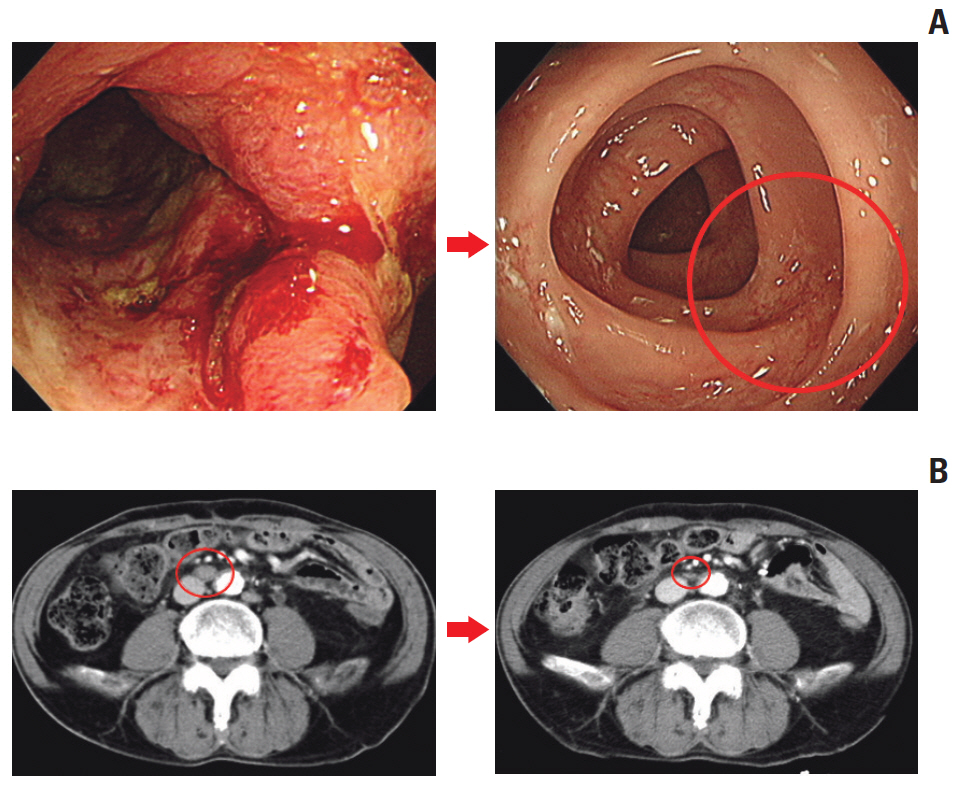

The median age was 60 years, and 78.8% were male. Thirty patients were dMMR/MSI-H and three had POLE mutations. The ORR was 24.2%, and all of the responders were dMMR/MSI-H. For 21 patients with MSI-H by PCR or NGS, the ORR was 28.6%. At a median follow-up duration of 16.3 months, median progression-free survival and overall survival were 3.9 and 13.2 months in all patients, and 8.1 months and not reached, respectively, in patients with MSI-H by PCR or NGS. Dose interruption and discontinuation due to treatment-related adverse events occurred in 4 and 2 patients, respectively, with no treatment-related deaths.

Avelumab displayed antitumor activity with manageable toxicity in patients with previously treated mCRC harboring dMMR/MSI-H. Diagnosis of dMMR/MSI-H with PCR or NGS could be complementary to IHC to select patients who would benefit from immunotherapy.